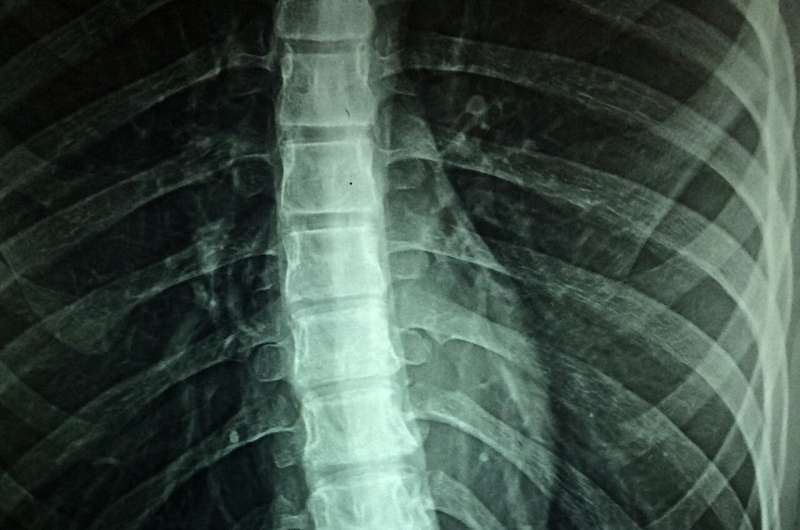

To avoid incorrect diagnosis of axial SpA, structural changes in the sacroiliac joints (so-called radiographic sacroiliitis) must be confirmed by X-ray with high specificity. Some patients’ radiographs do not yet show joint changes advanced enough to be radiographic axial SpA, although they may develop these changes years later. If an X-ray is negative but axial SpA is still suspected, magnetic resonance imaging (MRI) of sacroiliac joints is usually the next step.

Researchers evaluated sacroiliac radiographs of 361 patients with chronic back pain and suspected axial SpA who saw a rheumatologist for a diagnostic workup. The radiographs were evaluated using the modified New York criteria. Each patient was diagnosed with either axial SpA or not, by consensus of both the rheumatologist and a radiologist, based on the patient showing definite radiographic sacroiliitis. The doctors’ consensus judgment was the reference for comparison to the CNN’s evaluation.

Of the 361 patients in the study, pelvic images of 110 patients diagnosed with axial SpA, including 61 with radiographic and 49 with non-radiographic axial SpA, and 230 with no axial SpA, were evaluated by the CNN. These evaluations were compared to the traditional radiograph evaluation made by the doctors.

The CNN achieved 79% sensitivity for diagnosis of radiographic axial SpA and 94% specificity of radiographic sacroiliitis detection. Absolute agreement between the CNN and the reference on classifying patients with either radiographic or non-radiographic axial SpA was 85%. These results show that CNN is a reliable, accurate diagnostic tool for detecting radiographic axial SpA in patients with chronic back pain and has high specificity and acceptable sensitivity.